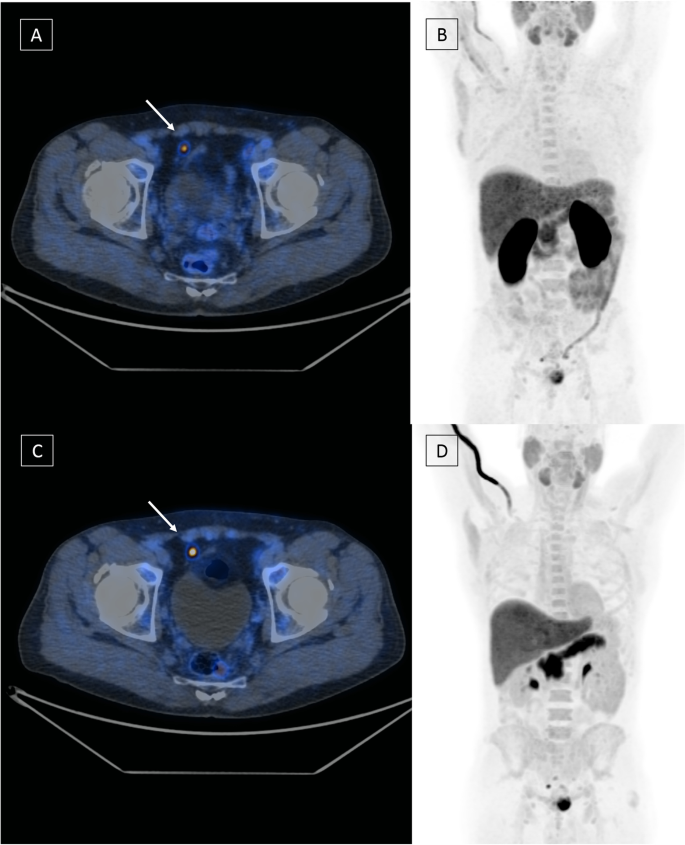

Serial F Fdg Pet Ct Scans Showing Complete Resolution Of Fdg Activity Download Scientific Diagram Pet Scanning For. Axumin PET CT is less sensitive for recurrent tumor detection in patients with a PSA level below 2ngml. Add to Pricing Basket.

18f Fluciclovine Pet Ct For Preoperative Nodal Staging In High Risk Primary Prostate Cancer Final Results Of A Prospective Trial Springerlink